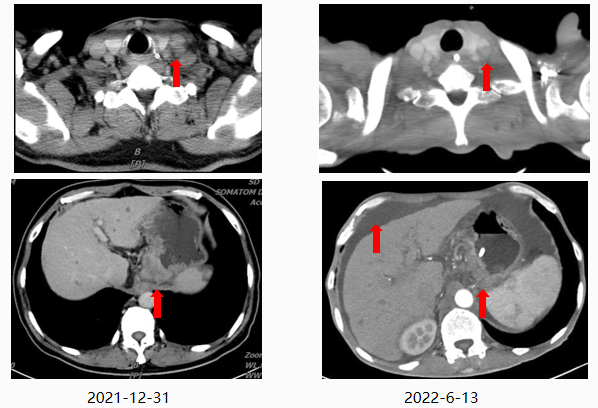

2022-06-13复查CT示伴腹膜后淋巴结转移、纵隔淋巴结转移,小网膜及肠系膜转移略加重,腹盆腔积液较前增多,考虑疾病进展,故更改治疗方案为白蛋白结合型紫杉醇200mg d1、100mg d8 2周期。

本例患者确诊食管胃结合部腺癌Ⅳ期,HER-2阴性,基于指南推荐以及循证证据,给予化疗联合免疫治疗一线治疗7周期,复查CT提示疾病进展,故联合放疗。在三种抗肿瘤治疗方式的联合作用下,患者出现CTIT,血小板下降至75×109/L。给予rhIL-11治疗10天疗效欠佳,血小板持续下降,且出现下肢水肿不良反应,改为rhTPO治疗7天后血小板降低得以改善。然而随着治疗周期的增加,患者在下一周期出现了更为严重的血小板减少症,血小板降至38×109/L,遂予以新一代血小板生成素受体激动剂(TPO-RA)海曲泊帕联合rhTPO治疗,血小板快速回升,保证患者按时按量的完成抗肿瘤治疗。此后患者复查CT再次提示疾病进展,重新评估病情后予白蛋白紫杉醇单药化疗,化疗过程中再次出现血小板下降。考虑rhTPO针剂注射治疗需住院或频繁返院,增加相关治疗成本,因此给予患者海曲泊帕7.5mg/天行院外治疗,有效且便捷地提升血小板,使患者顺利完成后续治疗。